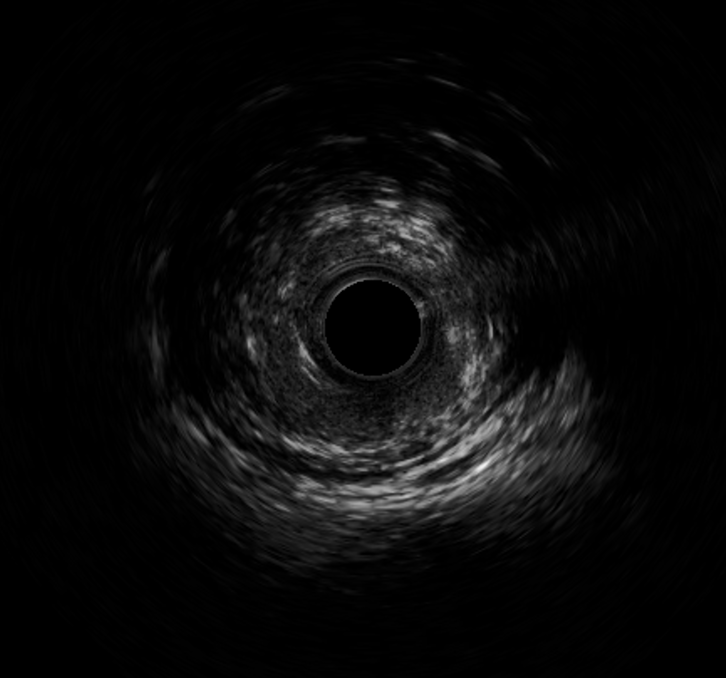

▲术后血管内超声

术前心电图同样反映出该病症的相关特征。入院后急诊冠脉造影发现,前降支近段存在50%局限性狭窄,中段节段性病变,且最重狭窄达到90%并可见明显的血栓影。为更精准把握血管内部情况,我院团队进一步行血管内超声检查,结果显示前降支中段可见纤维脂质斑块,最小管腔面积仅为2.11mm²,斑块负荷高达81.5%。面对如此复杂的病情,我院介入团队沉着冷静、有条不紊地开展救治工作,先进行球囊扩张,而后成功植入一枚3.0*30mm支架。术后再次通过血管内超声检查确认,支架贴壁、膨胀良好,最小管腔面积已提升至6.15mm²,手术结果十分满意,患者胸痛症状明显缓解。